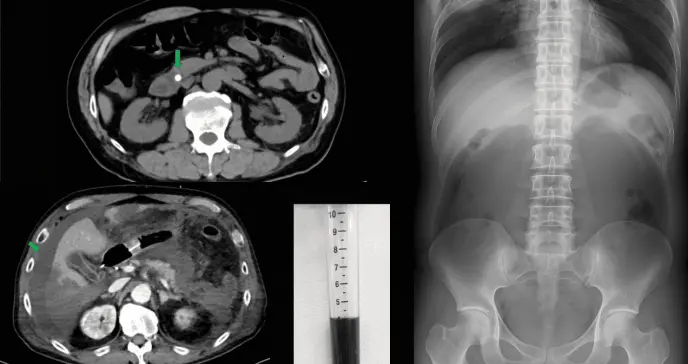

Tras una evaluación inicial en un centro menor, la tomografía computarizada (TC) abdominal reveló la presencia de un cálculo en el conducto colédoco (conducto que transporta la bilis desde el hígado y la vesícula biliar hasta el intestino delgado), acompañado de elevación marcada de proteína C reactiva (PCR) y amilasa pancreática.

Estos hallazgos condujeron al diagnóstico de colangitis aguda y pancreatitis aguda grave de origen biliar, por lo que se realizó una colangiopancreatografía retrógrada endoscópica (CPRE) con extracción del cálculo.

FIGURA 1: TC abdominal realizado en el hospital de referencia que demuestra un cálculo en el conducto biliar común (flecha verde) sin evidencia de ascitis. Foto: Caso Clínico - Kobori et al.